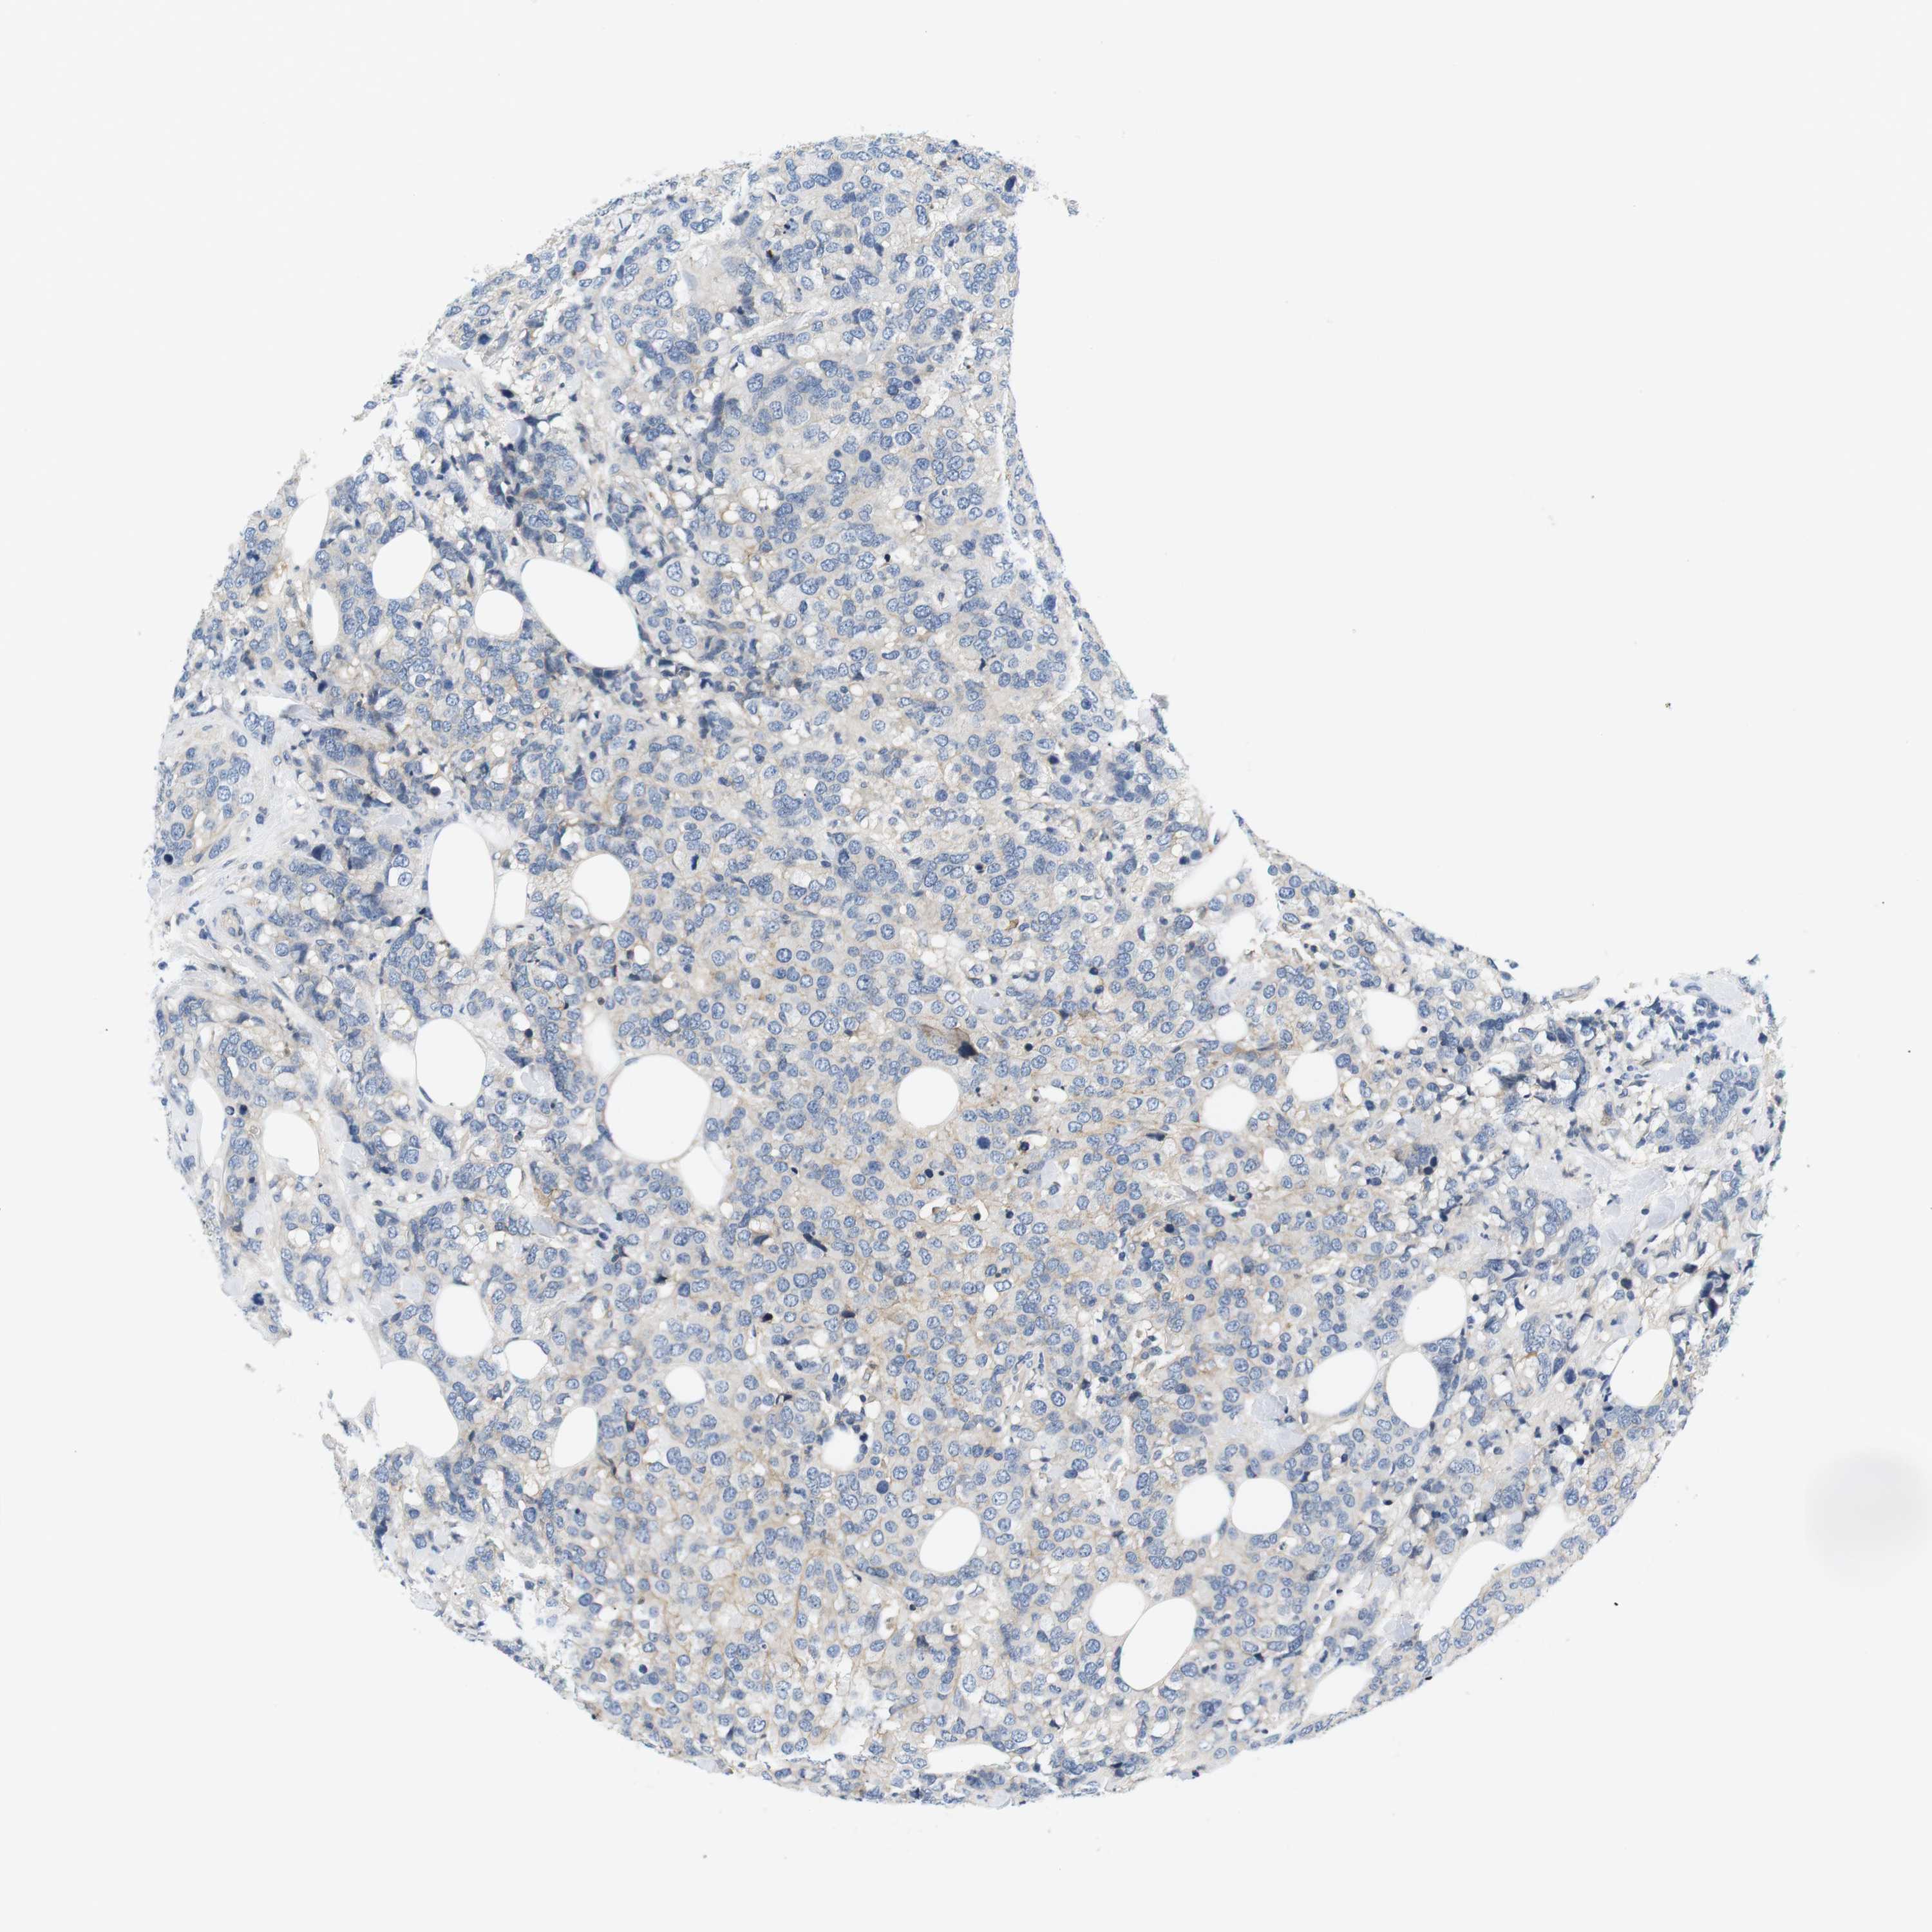

CANCER BREAST CANCER Show tissue menu

BRCA TCGA BRCA VALIDATION PROTEIN EXPRESSION

Breast cancer

Human cancer